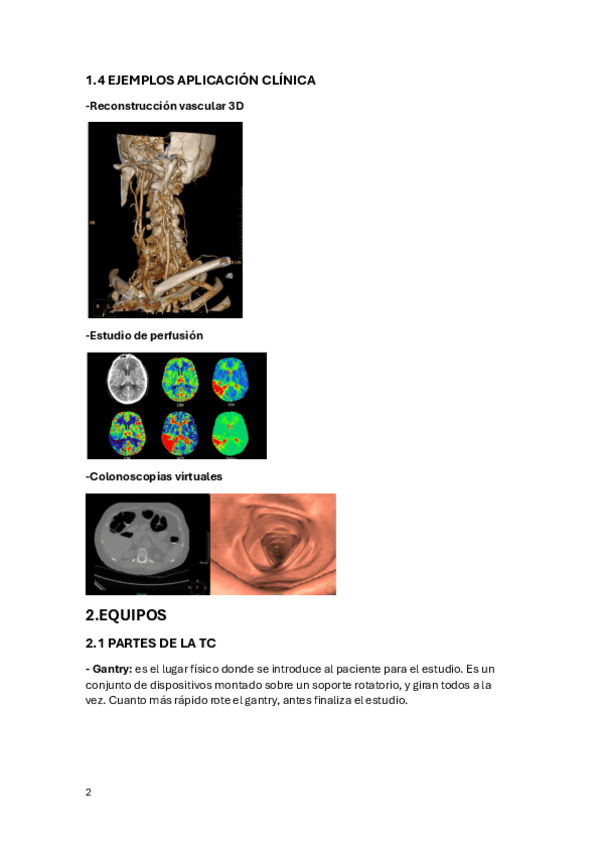

He publicado nuevos apuntes de 4º Diagnóstico Por Imagen: SIMULACRO-DIAGNOSTICO-POR-IMAGEN.pdf

6 páginas